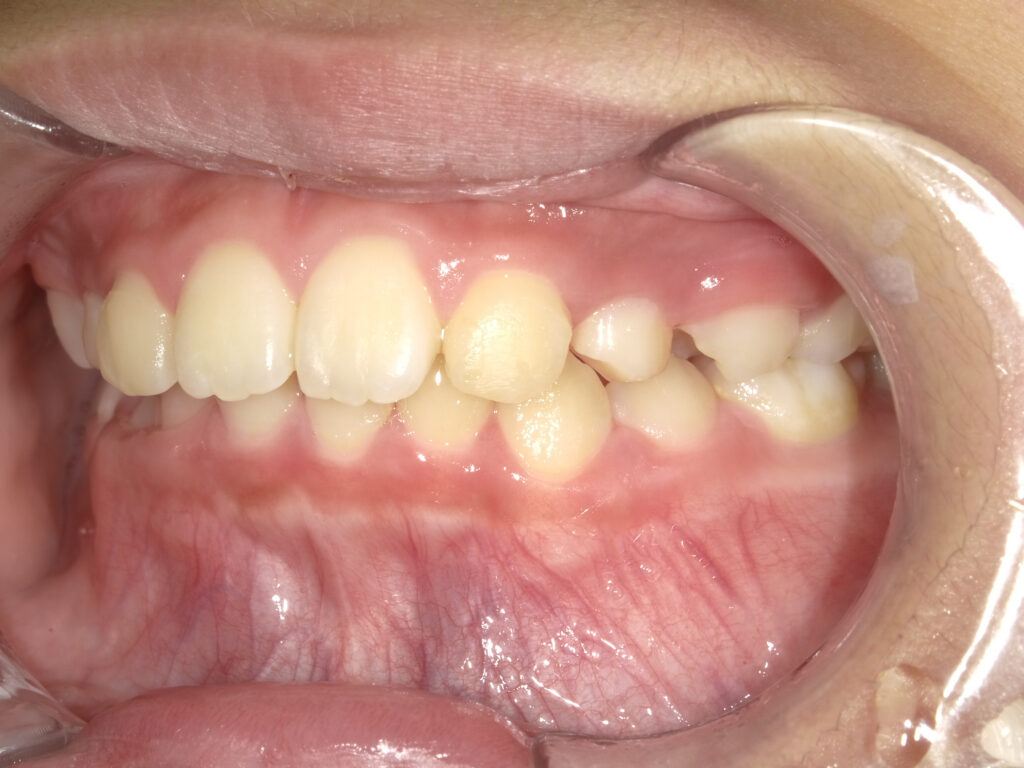

右側

治療後